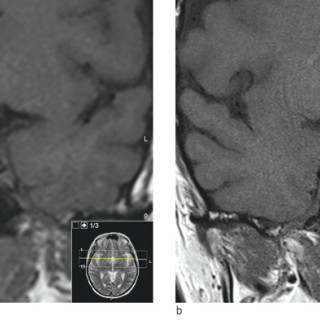

En yngre mann ble innlagt med venstresidige respirasjonsavhengige brystsmerter. Han hadde lett nedsatt allmenntilstand og feber. Det skulle bli et lengre sykehusopphold, der man diagnostiserte en uvanlig årsak til lungeaffeksjon. En tidligere frisk mann i slutten av tenårene ble via legevakt innlagt i sykehus etter ett døgn med venstresidige, respirasjonsavhengige smerter. Ved innkomst hadde han temperatur 37,6 °C, puls 117 slag/min, blodtrykk 104/57 mm Hg, respirasjonsfrekvens 24/min og perifer O2-metning på 94 % uten ekstra oksygentilførsel, og normale forhold ved klinisk undersøkelse...